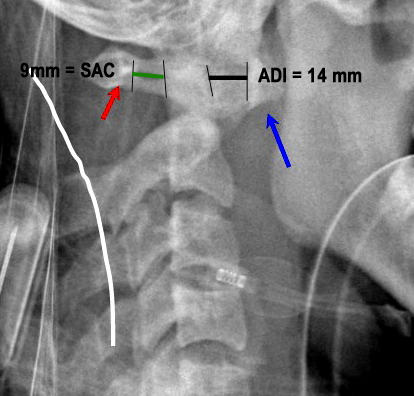

PADI>14mm

Boden and associates’ article presents compelling evidence that patients with rheumatoid arthritis and neurologic deterioration in C1-2 instability are more likely to achieve some improvement if the posterior atlanto-dens interval is greater than 10 mm on preoperative studies. All the patients in their series who had neurologic deterioration and a preoperative posterior atlanto-dens interval of greater than 14 mm achieved complete motor recovery.

Boden et al. “The most important predictor of the potential for neurological recovery after the operation was the preoperative posterior atlanto-odontoid interval (PADI). In patients who had paralysis due to atlanto-axial subluxation, no recovery occurred if the PADI was less than 10mm, whereas recovery of at least one neurological class always occurred when the PADI was at least 10mm. All patients who had paralysis and a PADI or diameter of the subaxial canal of 14mm had complete motor recovery after the operation.” They found no correlation with the anterior atlanto-odontoid interval (ADI) with the severity of paralysis or the potential for recovery.

Xrays to determine AADI and PADI:

- 3.5 mm on flex/ex

- PADI <14 mm more sensitive than AADI measurement for spinal cord compression in patients w/ RA. More sensitive for identifying patients at risk of neuro injury.

Surgery:

Xrays determine mechanical instability: c1-c2 relationship.

* AADI >9-10 mm= surgery due to risk of neurologic injury

* PADI <14 mm= surgery due to risk of neurologic injury

* 3.5 mm on flexion/ext views, though radiographic instability is common in RA and not necessarily indication for surgery.

PADI <14 mm more sensitive than AADI measurement for spinal cord compression in patients w/ RA. More sensitive for identifying patients at risk of neuro injury.

AAOS: patients with rheumatoid arthritis and neurologic deterioration in C1-2 instability are more likely to achieve some improvement if the posterior atlanto-dens interval is greater than 10 mm on preoperative studies. All the patients in their series who had neurologic deterioration and a preoperative posterior atlanto-dens interval of greater than 14 mm achieved complete motor recovery.